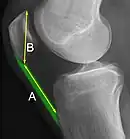

Insall-Salvati ratio (A divided by B).[6]

The Insall-Salvati ratio helps to indicate patella baja on lateral X-rays, and is calculated as the patellar tendon length divided by the patellar bone length. An Insall-Salvati ratio of < 0.8 indicates patella baja.[6]